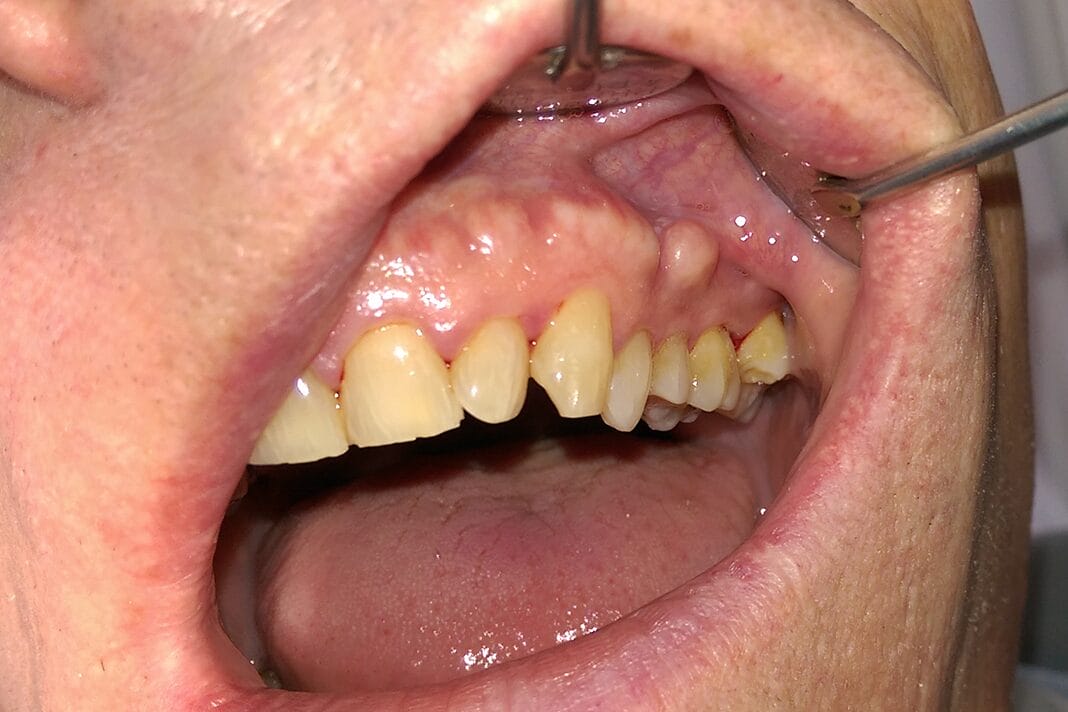

Buccal exostosis occurs on the buccal, or cheek side, of the mouth. Bony exostoses are not usually present until the late teens and early adult years in approximately 3% of the adult population, occurring more commonly in females. Many bony exostoses will continue to grow slowly throughout life.4

These hard nodules consist of compact bone when small and cancellous bone when larger. The two most common intraoral bony growths are the torus palatinus (TP) and the torus mandibularis (TM).2 Oral exostoses can also occur on the buccal regions of the mouth, as well as the anterior regions, but are less common.2,3

The torus mandibularis occurs on the lingual aspect of the mandible, typically bilaterally, around the premolar and canine regions.2,3 This variation of bony overgrowth occurs in a range of 5% to 40% of the population.4